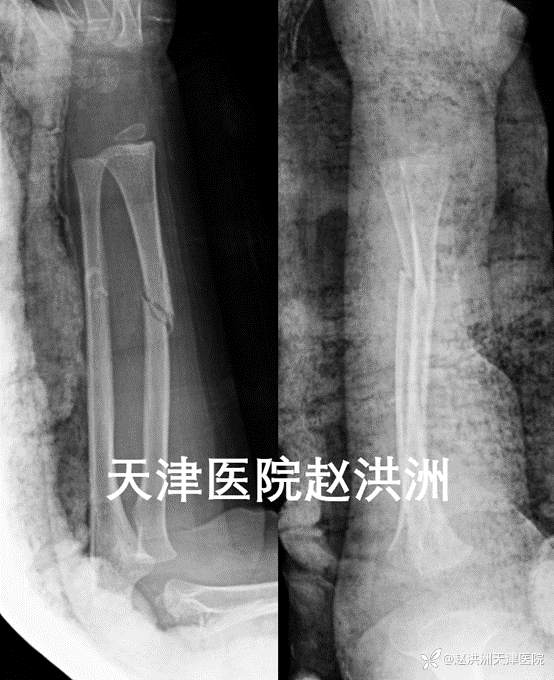

急诊X光片,尺桡骨干双斜形骨折

急诊复位后,骨折端对位对线可